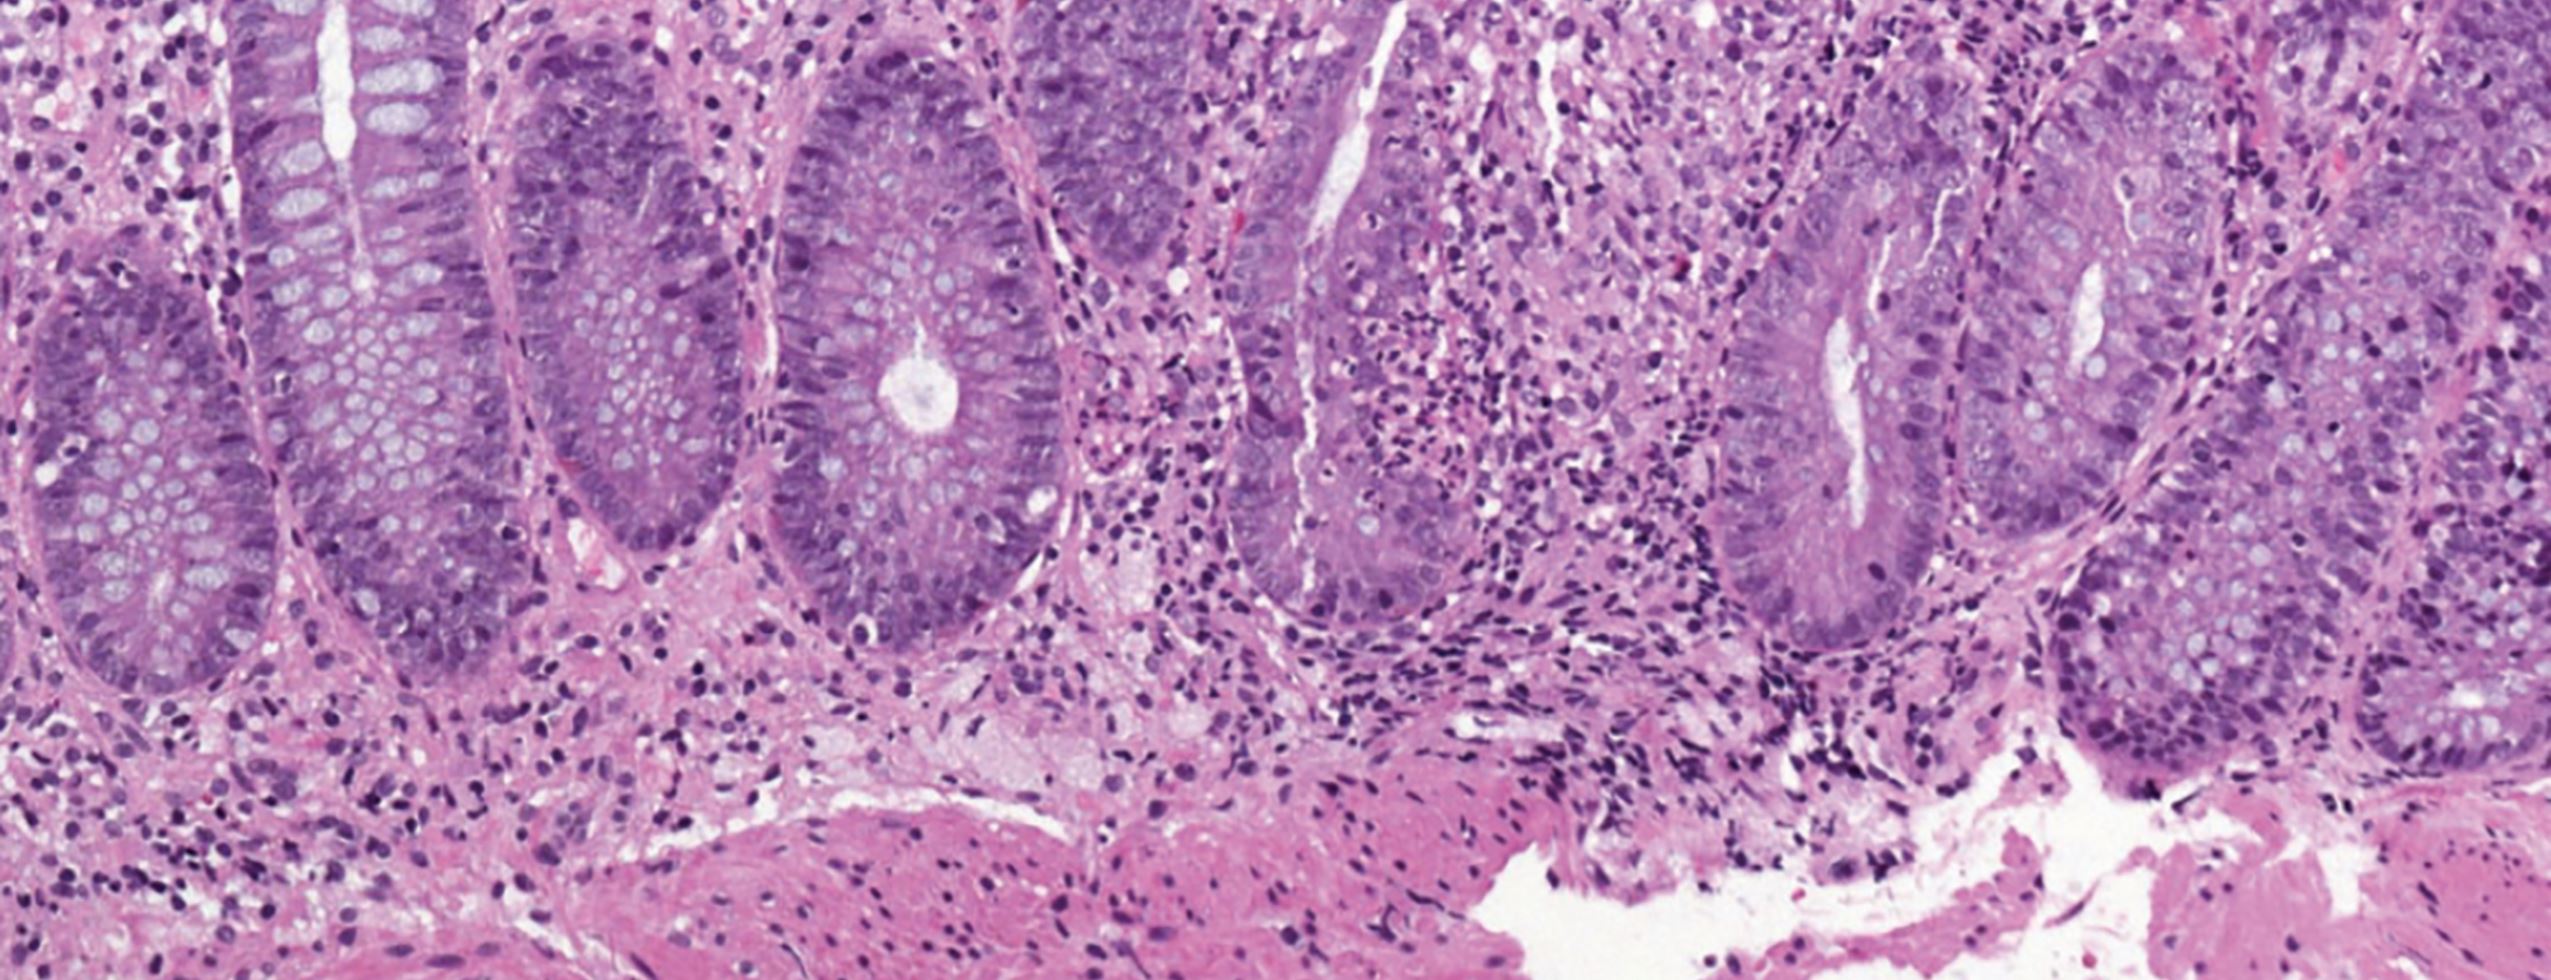

© Langner C. Management von CED-Patienten. Wien klin Mag. 2016;19,118-20